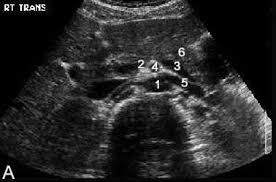

What Do Kidney Stones Look Like On Ultrasound. A kidney ultrasound creates images from sound waves that return from the kidney tissue. Their appearance can vary depending on what the kidney stones.

However kidney stones may not be visible unless they are located where the ureter and bladder meet. Ultrasound can be efficient in visualizing clear uric acid stones and obstructions caused by any type of kidney stones. Most scientist agree on the fact that ultrasound simply is not sufficient enough to detect very small kidney stones. Kidney stones are little crystals that form into pebble like stones in the kidneys and some may block the urinary tract.